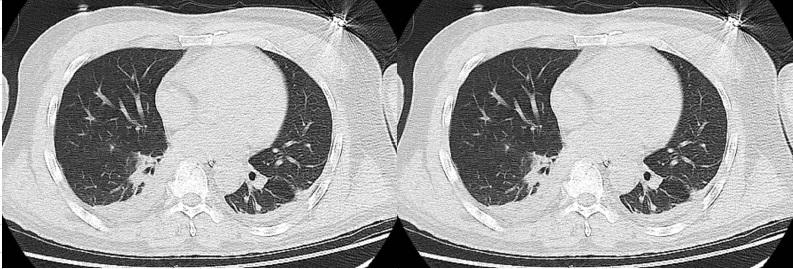

患者,男,42岁,因“爆炸烧伤致头颈、躯干、四肢疼痛2 d”于2020年6月15日由外院转入浙江大学医学院附属第二医院滨江院区急诊ICU。入院诊断:烧爆复合伤:1.头面部、双上肢、髋部及左下肢深二度烧伤(38%)2.肺部爆震伤。入院查体:患者神情,精神软,急性生理和慢性健康状况评分Ⅱ(APACHEⅡ评分)9分, 体温37.6℃, 心率115次/min, 呼吸24次/min鼻塞吸氧(5 L/min),氧饱和度95%~99%,心肺听诊阴性,腹软,无压痛反跳痛,肠鸣音2~3次/min,颜面部及胸前可见大片烧伤,予阴离子纱布覆盖,双上肢及左下肢纱布包裹,可见少许渗液。入院给予清创换药,留置鼻肠管行肠内营养,哌拉西林他唑巴坦4.5 g/8h抗感染,输注血浆及白蛋白等对症治疗;并完成术前相关检查。入院后第3天开始出现氧合指数下降:由入院当天的325降至178;氧疗方式改为经鼻高流量吸氧:流量50 L/min,吸入氧体积分数45%;行胸部CT与入院当日相比未见明显加重(图 1):两下肺少许渗出,两侧少量胸腔积液;肺部超声评分(总分36分)由入院当天的19分上升至第3天的26分。同时患者出现高热,血压下降,炎症指标上升,考虑创面细菌入血导致的感染性休克,予调整抗生素方案(加用替加环素)并进行液体复苏:当天24 h正平衡2 600 mL,考虑患者入院后肺水明显增加且合并肺部爆震伤,我科采取超声指导下的限制性液体复苏策略:①予小剂量去甲肾上腺素稳定血压,维持脏器功能循环;②为尽量减少肺水的进一步增加,予肺部超声评估下的限制性液体复苏,关注肺部超声评分和氧合指数的变化。每日行肺部超声,根据肺部超声评分降低肺水含量(见图 2),适当利尿,治疗期间液体负荷量及氧合指数见图 3。患者入院后第6天行“双上肢切痂、异体皮覆盖术及头面躯干部清创术”,术后患者机械通气情况下氧分压仍偏低,考虑患者后期需多次手术及肺部情况给予气管切开术。术后循环呼吸逐渐稳定,经过烧伤科四次切痂及植皮手术,多学科团队综合治疗,患者3周顺利脱机并拔除气切套管;4周后患者转当地医院继续康复治疗。

| 图 1 患者入院当日及第3天胸部CT变化 |